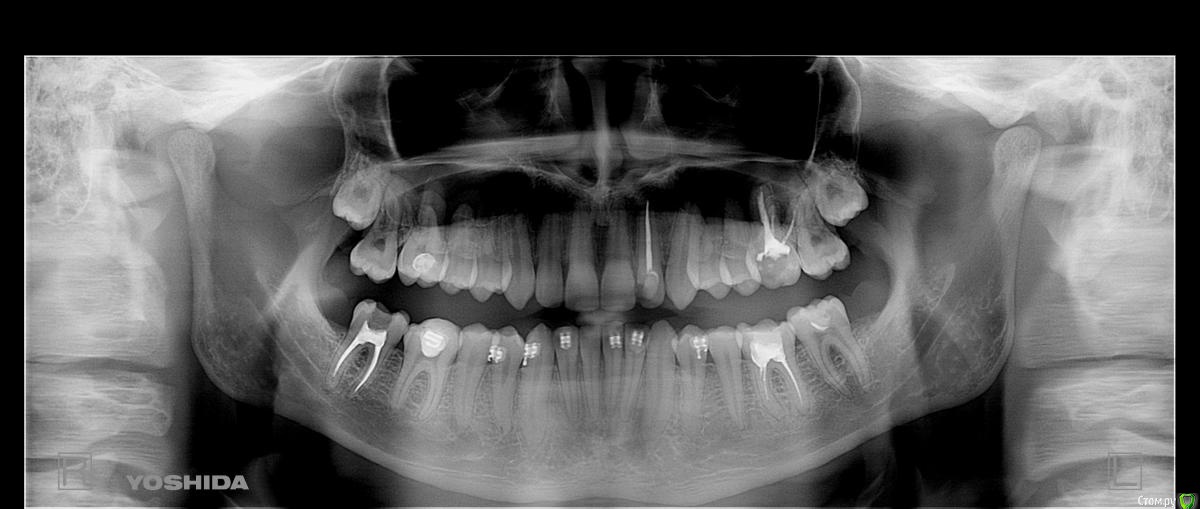

babledy Опубликовано 19 октября, 2015 Поделиться Опубликовано 19 октября, 2015 Доброго времени суток. Зовут меня Ростислав, мне 18 лет, в данный момент учусь и живу в Киеве. То что у меня проблемы с прикусом знал еще с 15 лет, до этого уже один раз проводилось лечение брекетами, но я остался категорически не доволен результатом. На предпоследнем посещении мне сказали что при снятии брекетов будут спиливать около 3-4 миллиметров передних зубов на НЧ и в связи с этим на последнее посещение я не пришел( До сих пор хожу с замочками на НЧ). После такого неудачного лечения я надеялся на профессионализм врачей в столице, но не тут то было. После 4 консультаций в разных клиниках, в первых трех врачи посмотрели меня, не сделав ни одного снимка и диагноз был таков - глубокий дистальный прикус, переразвитие верхней челюсти и недоразвитие нижней(их задача как я понял - просто исправить прикус, не учитывая черты лица). Я категорически не согласен с этим, хоть я и не врач, но как у меня может быть переразвитие ВЧ, если профиль моего лица вогнутый? В последней клинике мне удалось откровенно поговорить с врачом, я рассказал ей что меня не устраивает и она направила меня сделать два снимка. Она сказала нечто иное, что НЧ у меня наоборот нормально развита и так же она мне сказала, что когда мне хотели спиливать нижние передние зубы, то это таким образом мне хотели вылечить кривую Шпея. На консультациях я ожидал, что мне как минимум скажут о недоразвитии ВЧ, скажут что нужно двигать зубы ВЧ вперед, чтобы поправить профиль. Дорогие врачи, к чему я все это завел. Я уже около недели хожу никакой, разочаровался что меня уже вылечить не смогут так, как мне того хотелось или же просто эти "врачи" не хотят усложнять себе жизнь моим нормальным, правильным лечением? Действительно ли у меня переразвитие ВЧ или же нет и какой реальный диагноз моего прикуса, можно ли его лечить? Ссылка на комментарий

m.d.n Опубликовано 19 октября, 2015 Поделиться Опубликовано 19 октября, 2015 Лечить можно, если хотите профиль лицо и тд- то ортогнатическая хирургия вам в помощь. дело не в размере челюстей а в их положении относительо основания черепа Ссылка на комментарий